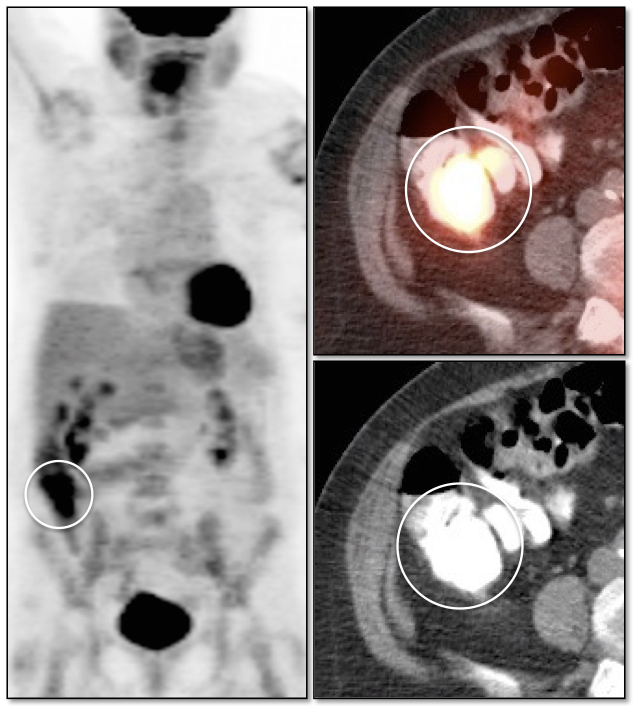

Lung Nodule Identification:

NAC images can occasionally be useful in identifying mild to moderately FDG-avid lung nodules, especially those located in the lung periphery or lung bases.